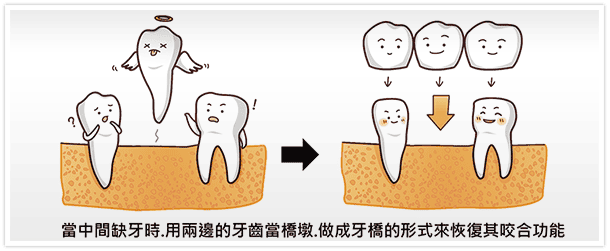

Sunny一直以為… 作假牙是這樣的(如下,不過這圖少了植牙?)

Sunny原以為做一顆單顆假牙就要犧牲旁邊兩顆健康的牙齒